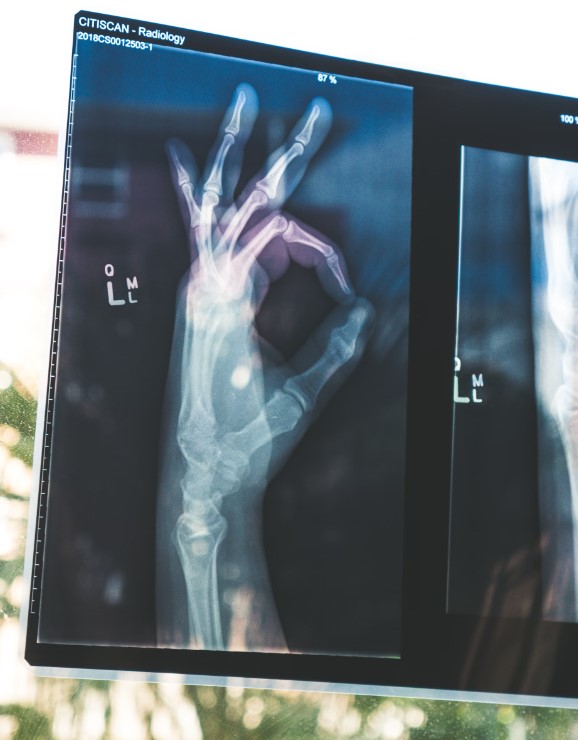

뼈 건강은 나이가 들면서 점점 더 중요해집니다. 특히 골다공증이나 관절염 같은 뼈 관련 질환을 예방하기 위해서는 평소에 뼈에 좋은 음식, 영양제, 약초, 그리고 적절한 운동을 꾸준히 하는 것이 중요합니다. 아래에서 뼈 건강을 지키는 방법을 소개합니다.